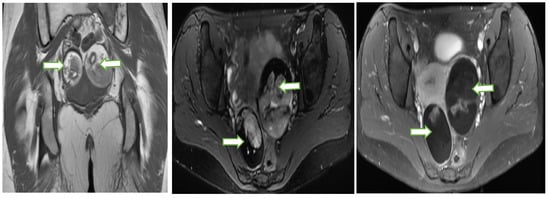

4.2. Magnetic Resonance Imaging (MRI)

- MRI is regarded as the gold standard for local delineation of most gynecological malignancies owing to superb soft tissue contrast and resolution without exposing the patients to ionizing radiations. In addition, DCE and DWI provide additional data regarding tissue perfusion and cellular density, respectively.